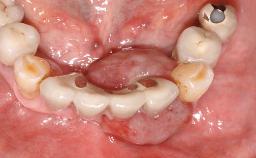

Surgical treatment of a 67-year-old male patient exhibiting an extended edentulous space in the anterior maxilla after the removal of three hopeless incisor teeth.

The video demonstrates implant placement using a surgical stent according to the principle of prosthodontically driven implant placement. The deficient ridge is augmented with locally harvested autologous bone chips, a superficial layer of xenogenic DBBM particles and a resorbable collagen membrane. The surgery is completed with a precise, tension-free primary wound closure.

The case concludes with the presentation of the final prosthesis and the esthetic outcome, demonstrating stable soft tissue conditions and stable bone crest levels at the 3-year follow-up.

Prosthesis Type FDP